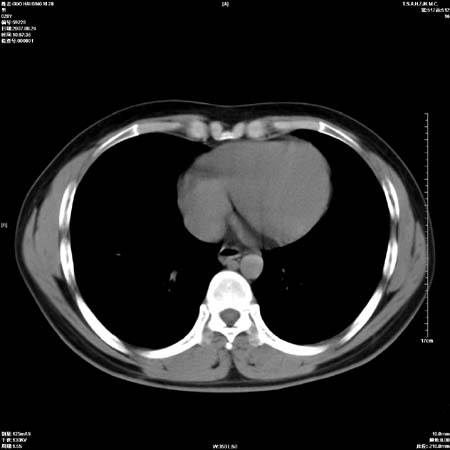

男性,28岁,体检发现左肺病变,患者只有背部隐痛感,哀哉,真不忍心下诊断啊。

左肺门区软组织肿块,左肺上叶支气管开口消失,纵隔内见肿大淋巴结,考虑左中心型肺部,可以做纤支镜取病理确认.

左肺肺门区肿块影,分叶明显,左肺上叶支气管开口受压,纵隔内见肿大淋巴结,考虑左中心型肺癌。

支持左上叶中央型肺癌伴纵隔淋巴结转移.

左上叶中央型肺癌伴纵隔淋巴结转移

左上叶中央型肺癌伴纵隔淋巴结转移.

肿块形态影像支持左上叶中央型肺癌伴纵隔淋巴结转移。

支持左上叶中央型肺癌伴纵隔淋巴结转移

支持左肺上叶中央型肺癌伴纵隔淋巴结肿大.

左侧中心型肺癌纵隔淋巴结转移。我们见一例16岁男孩,已经脑转移了。

左肺门区分叶状软组织肿块,纵隔内有肿大淋巴结,诊断肺癌应该问题不大。

肺癌并纵隔淋巴结转移。

左上叶中央型肺癌伴纵隔淋巴结转移.苦命!

左肺中心型肺癌并纵隔淋巴结转移!考虑为小细胞肺癌,没有手术机会了,只能进行放化了,疗效不错,但极易复发。没办法,现在肿瘤年轻化越来越明显了。

左上肺癌伴纵隔淋巴结转移.